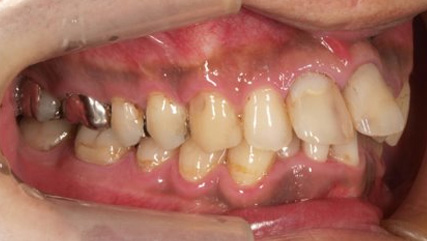

上顎前突といわれ、上顎の前歯が唇側に出ている状態を言います。

前歯が出ることで見た目の問題もありますが、口を閉じることができない、口呼吸をしてしまう、外傷などのリスクがあります。

日本人に叢生の次に多い不正咬合と言われており、自然に治ることはありません。また上の前歯が出ている事だけが気になるかもしれませんが、多くの場合、上顎の奥歯の位置に問題があることが多く、部分矯正でなく根本的な治療をした方がいい場合が殆どです。

口を閉じることができないことで、鼻呼吸でなく口呼吸をしてしまい、結果、成長期の場合顎の骨の成長を邪魔してしまうとも言われております。その他、口呼吸はアトピーなどを含むアレルギー症状の悪化、風邪を含むウイルス性の感染症にかかりやすいなどのリスクも増大してしまいます。

歯並びだけでなく全身への影響も多い為、早期の治療をおすすめ致します。

治療前

治療終了前